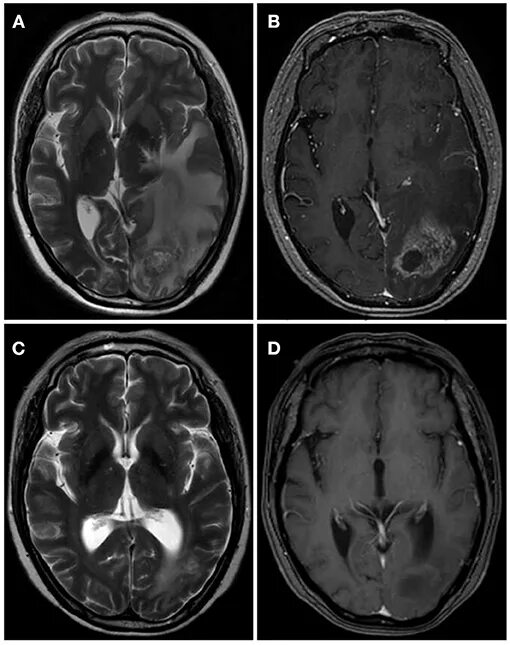

Гамма нож метастаз